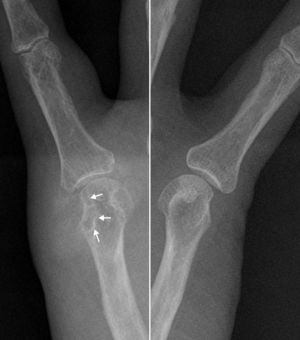

En la ecografía no se evidenció derrame, pero sí una lesión de las partes blandas, parcialmente definida, y de ecoestructura heterogénea, con áreas hiperecoicas. La tumoración estaba en contacto con la cortical ósea del metacarpiano, que se mantenía intacta, salvo en una zona donde se objetivó una franca erosión, con la lesión de partes blandas proyectándose dentro de la cavidad medular (fig. 1). Ante los hallazgos de la ecografía, se analizó la radiografía, que confirmó el aumento de las partes blandas periarticulares, con muy alta densidad, acompañado de erosión en la cabeza del metacarpiano, que como dato característico tenía un margen escleroso (fig. 2). Estos hallazgos ecográficos y radiográficos indicaron un tofo gotoso periarticular con erosión ósea asociada. La punción ecoguiada del posible tofo mostró un material denso blanquecino, que al microscopio de luz polarizada puso de manifiesto los cristales de urato monosódico (fig. 3).

Radiografías centradas en la quinta articulación metacarpofalángica de ambas manos que permite valorar comparativamente la erosión ósea de margen escleroso (flechas) con el aumento de las partes blandas, de alta densidad, en la vertiente medial de la cabeza del metacarpiano derecho. No hay afectación del espacio articular.